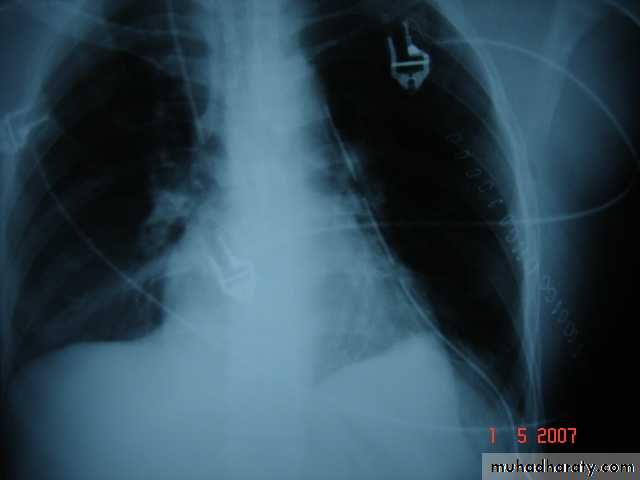

• Treatment

• Surgical• A-Inoculation means to remove it intact.

• B-Aspiration &evacuation technique

• C-Wedge resection or excision of the cyst with adjacent lung tissue.

• D-Segmentectomy ,Lobectomy or Pneumonectomy (rare ).